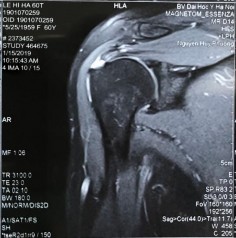

Bệnh nhânn nữ 60 tuổi, tiền sử khoẻ mạnh. Bệnh nhân xuất hiện đau vai phải cách đây đã lâu, đau nhiều về đêm và khi đưa tay lên cao. Bệnh nhân đã khám và điều trị tại bệnh viện tỉnh nhiều lần nhưng không đỡ. Bệnh nhân đến khám và nhập bệnh viện Đại học y Hà Nội ngày 15/01/2019. Khám thấy đau âm ỉ vùng vai, vai hạn chế giạng và đưa trước khoảng 60 độ, hạn chế xoay trong và hạn chế xoay ngoài. Khám các test phát hiện chèn ép khoang dưới MCV và tổn thương gânn chóp xoay thấy: Neer test (+); Speed test (+); Jobe test (+); Patte test (+); Drop arm test (-); Bear Hug test (-), trên phim MRI chụp trước mổ có hình ảnh rách nhỏ gân chóp xoay. Bệnh nhân được tiến hành phẫu thuật khâu gân chóp xoay ngày 16/01/2019 bằng 01 neo. Đánh giá điểm ASES trước mổ và sau mổ là 11,67 và 98,33 điểm UCLA sau mổ là 33, bệnh nhân rất hài lòng và cảm thấy tốt hơn rất nhiều so với lúc chưa mổ.

Hình phụ lục 1A: Phim CHT bệnh nhân trước mổ cho thấy rách nhỏ gân trên gai (Nguồn: BN nghiên cứu)